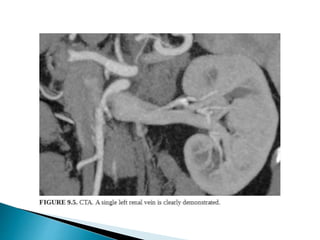

 CT is the preferred imaging due to better spatial resolution

and sensitivity to vascular calcifications and renal stones.

 CTA >> MRA

1. Distinguishing single/two main renal arteries.

2. Anatomy and to identify the point at which first branch

occurs.

3. Renal venous anatomy,

4. Tiny polar accessory arteries.

 Renal venous anatomy

◦ Retro-aortic/circum-aortic left renal vein.

◦ Duplicated right renal veins

◦ Distance between junction of vein with IVC and first

bifurcation

◦ Renal venous tributaries: adrenal/lumbar/gonadal

veins.